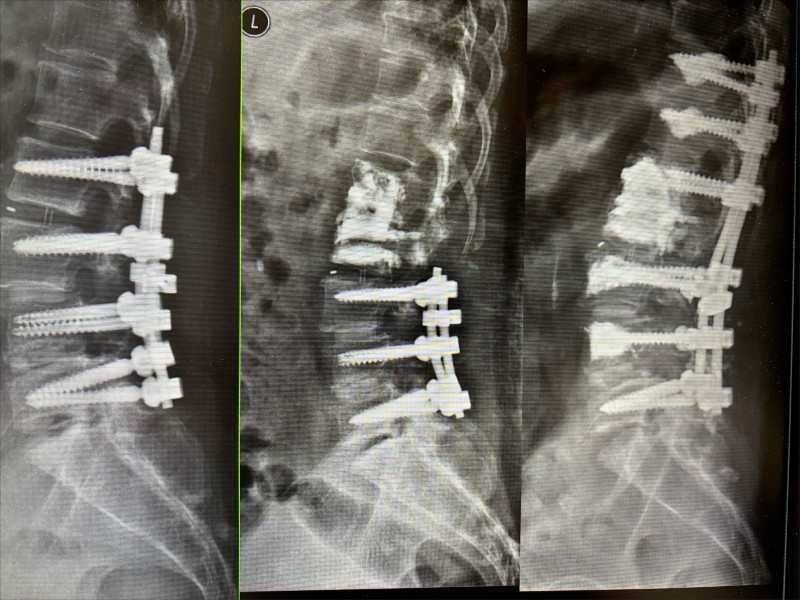

Cervical Spine Treatment Cases 精彩回顧 患者高爾夫球影片親自見證 2025.01.17 椎管狹窄曾經很難很難的病也有一線曙光 2025.01.19 2025.01.20 27歲陳小姐的巨大椎間盤突出康復之路 2025.01.23 2025.01.30 嚴重腰椎滑脫與椎管狹窄的重生之路 2025.02.05 嚴重心悸伴隨視力模糊跟血壓飆升 2025.02.07 頸椎脊髓壓迫導致手麻跛行掰咖 2025.02.11 椎間盤突出合併椎管狹窄的奇蹟之旅 2025.02.12 巨大椎間盤突出治療醫案 2025.02.13 擺脫腰痛束縛原來是椎間盤突出 2025.02.18 L小姐的交感神經症候群從痛苦折磨到重生 2025.02.19 半年無法站立原來是椎間盤巨大突出 2025.02.21 2025.02.23 2025.02.25 ← 上一頁 28 29 30 31 下一頁 →